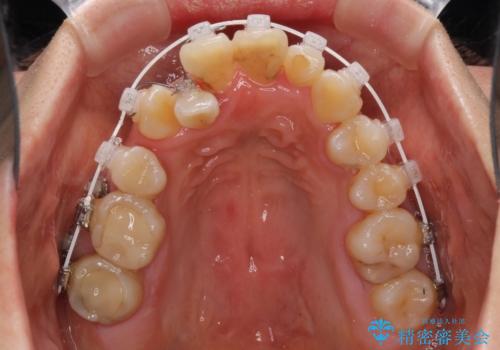

狭い上顎骨を拡大 著しい叢生を抜歯矯正で改善

骨格的に上顎は狭く、下顎は右側にシフトしていたため、右側臼歯はクロスバイトとなっていました。

上顎骨を急速拡大装置により拡大し、ワイヤー装置による抜歯矯正治療を行うこととしました。